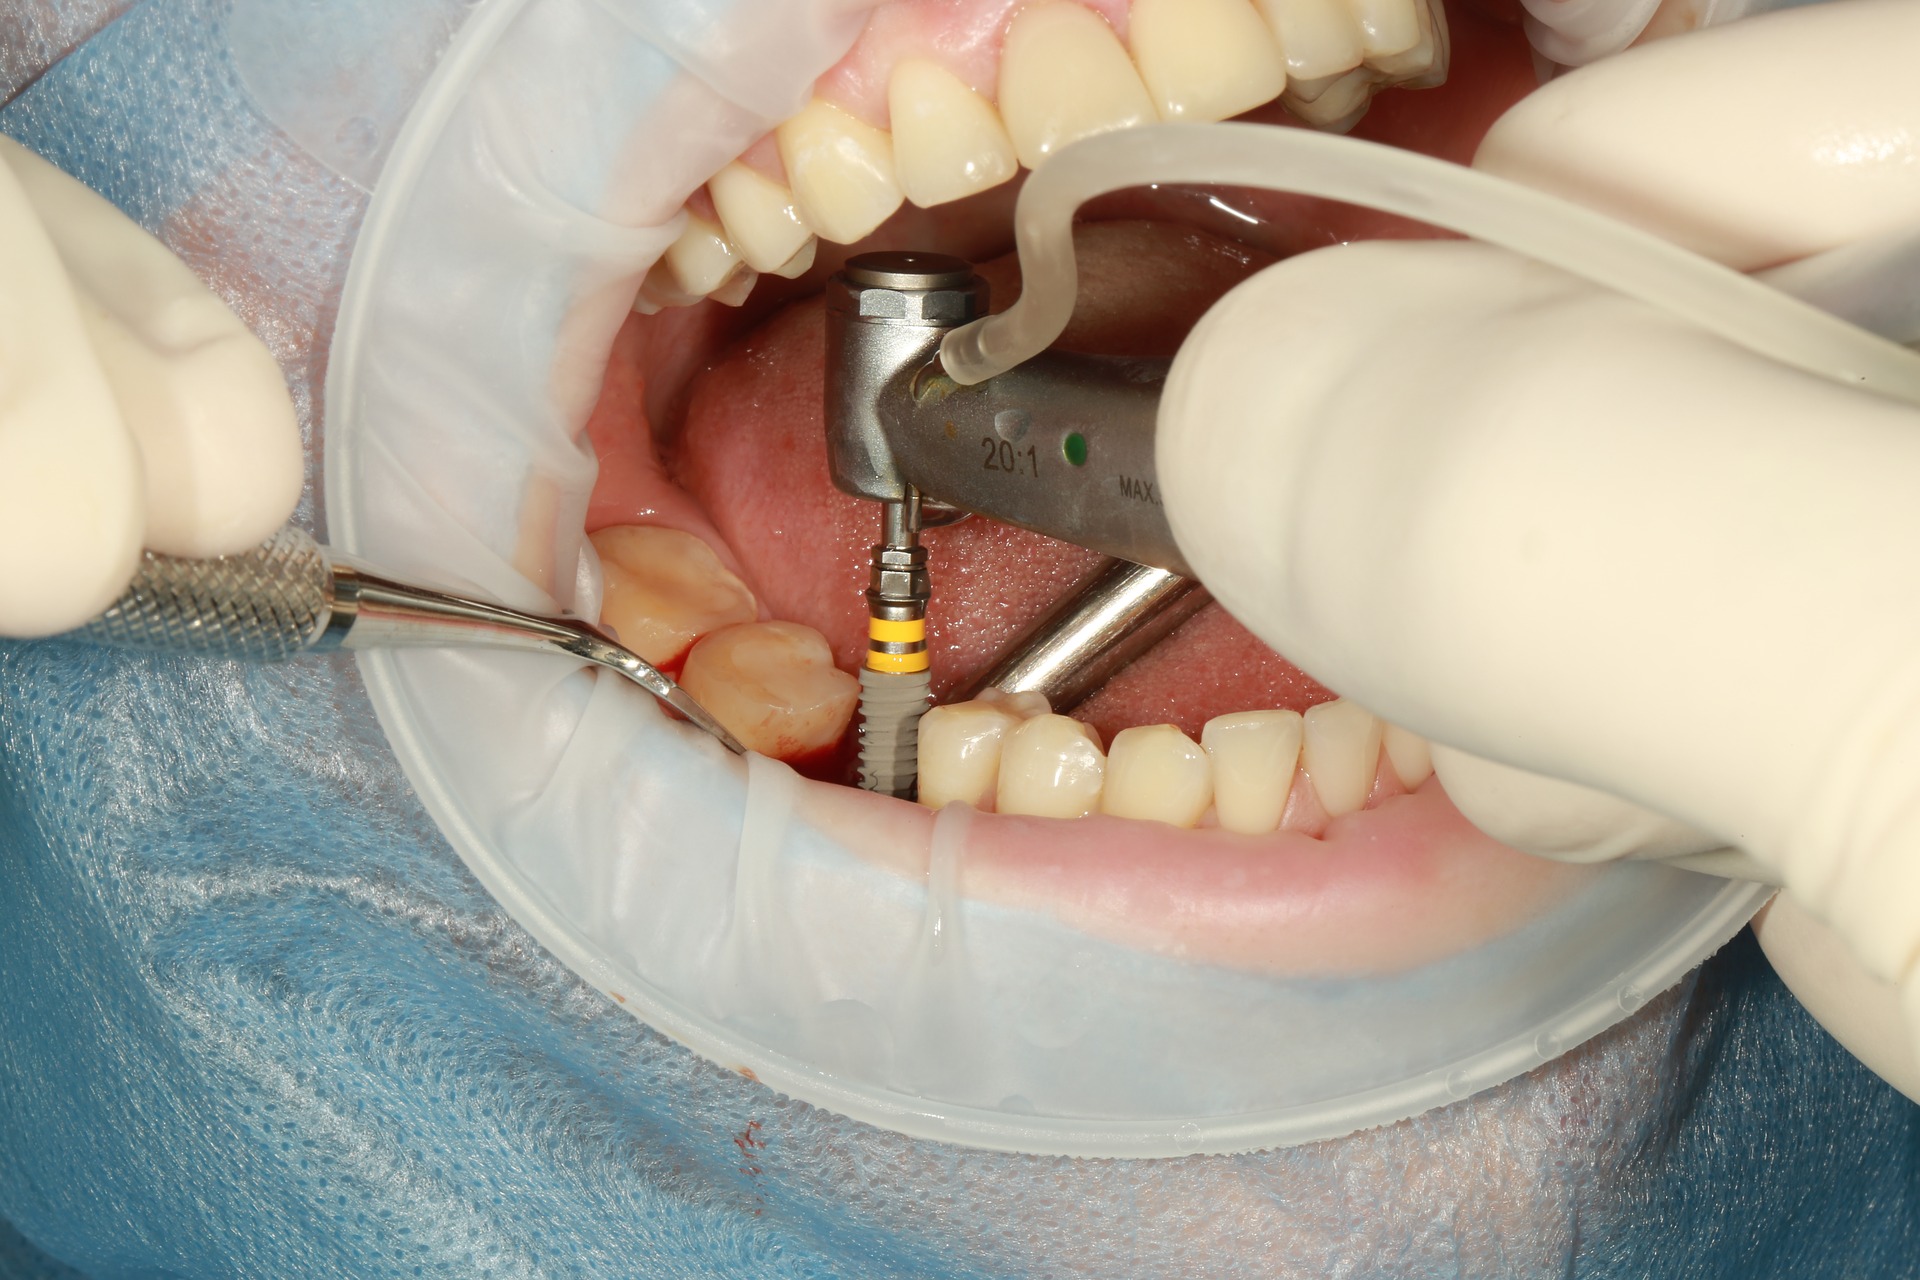

Implanttileikkaus

Leikkauskäynnillä leikaluuhun kiinnitetään titaaninen keinojuuri, joka jätetään luutumaan paikalleen.